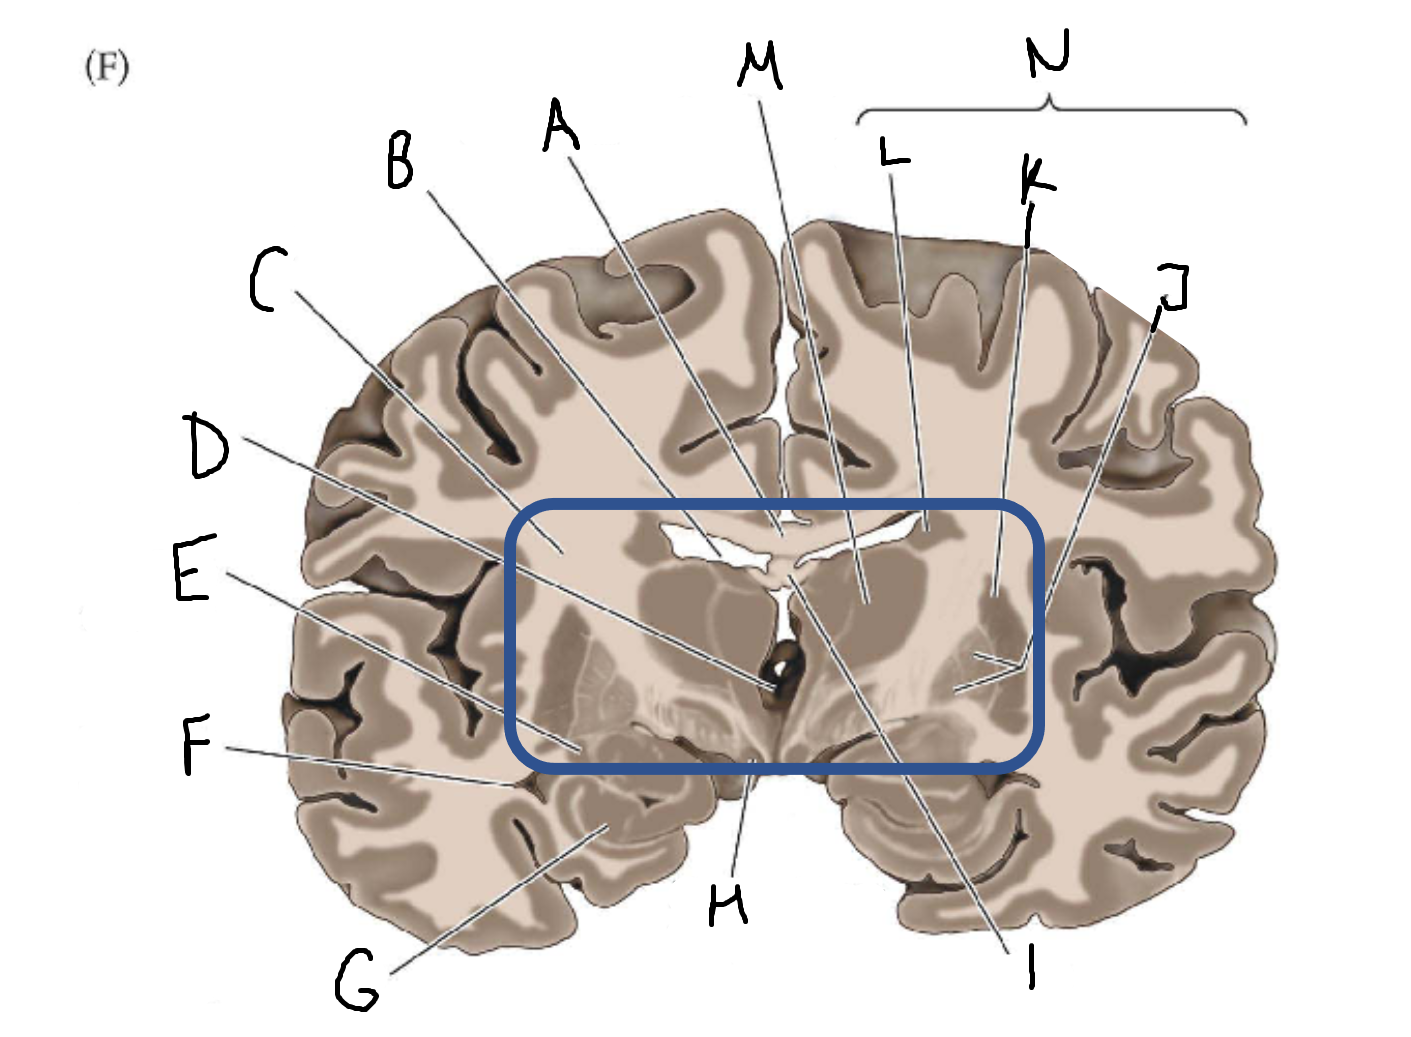

A

corpus callosum

B

lateral ventricle

C

internal capsule

D

third ventricle

E

tail of caudate nucleus

F

lateral ventricle

G

hippocampus

H

mammillary body

I

fornix

J

globus pallidus

K

putamen

L

caudate

M

thalamus

N

basal ganglia